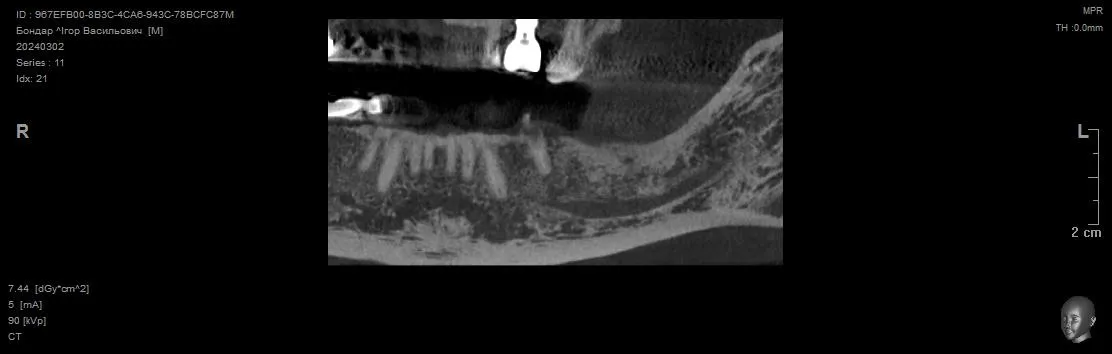

Видалення зуба 3.4 + Імплантація 3.4 3.5 3.7. Формувачі ясен. Система Neobiotech